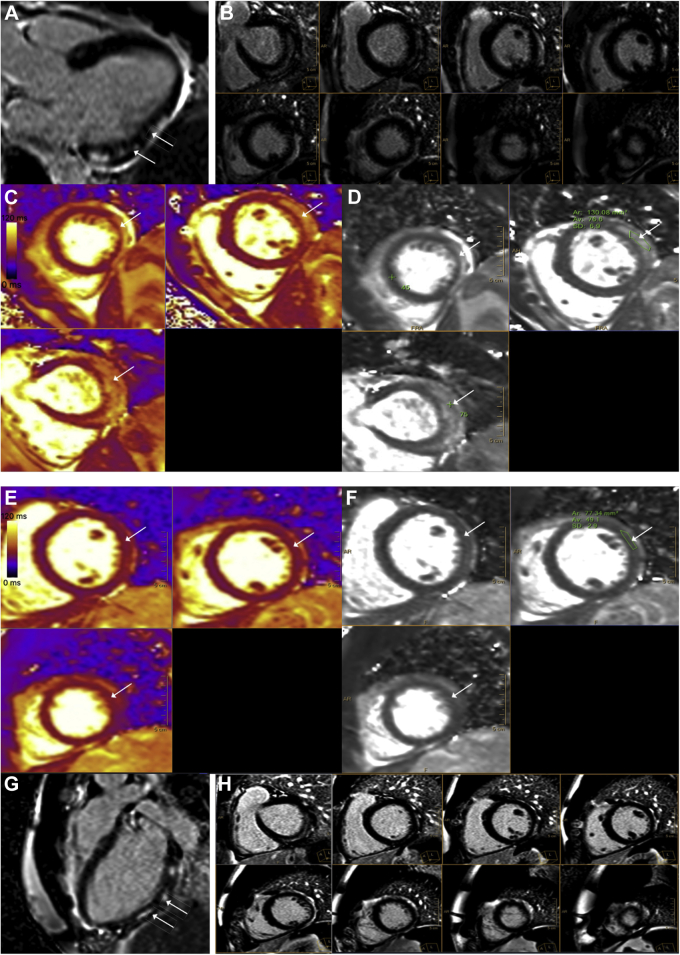

, view video online) of right coronary artery showed normal intravascular morphology with minimal lipid burden. Cardiac magnetic resonance (CMR) imaging demonstrated predominantly subepicardial enhancement of the basal to mid inferolateral wall and the apical lateral wall (Fig. 2, A and B), suggestive of myocarditis. The enhancement also included pericardium adjacent to the affected myocardium, suggestive of concomitant pericardial involvement and myopericarditis. The T2 signal (Fig. 2, C and D) was increased to 77 ms (for our clinical reference range, the value of 45 ± 6 ms is used for abnormal values, consistent with the Society of Cardiovascular Magnetic Resonance recommendation1) in the lateral wall, indicating presence of edema and acute inflammation. There was mild left ventricular systolic dysfunction (left ventricular ejection fraction: 52%) with mild hypokinesis of the lateral wall of the left ventricle (Video 4

Figure 2.

Cardiac magnetic resonance (CMR) imaging on 1.5T. (A, B) Late gadolinium enhancement imaging in (A) 3-chamber view and (B) short-axis view shows areas of patchy, mid to epicardial enhancement in the basal, mid, and apical lateral and inferolateral wall. (C, D) T2 maps in the short-axis projection show prolonged T2 relaxation times in the anterolateral and lateral wall, consistent with edema. For our clinical reference range, the value of 45 ± 6 ms is used for abnormal values consistent with the Society for Cardiovascular Magnetic Resonance recommendation.1 Follow-up cardiac magnetic resonance on 1.5T. (E, F) Late gadolinium enhancement imaging in 3-chamber- and short-axis view shows small interval decrease in late gadolinium enhancement. (G, H) T2 maps in the short-axis projection show resolution of the previously increased T2 signal. For our clinical reference range, the value of 45 ± 6 ms is used for abnormal values, consistent with the Society for Cardiovascular Magnetic Resonance recommendation.1